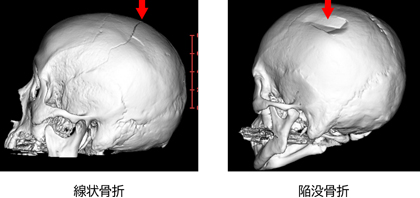

頭蓋骨骨折

頭に外力が加わり、頭の骨が折れると頭蓋骨骨折となります。陥没骨折(頭蓋骨が折れて凹む状態)によって、脳への圧迫を認める場合や頭蓋骨の外と内が開放して感染の危険がある場合は手術が必要となります。